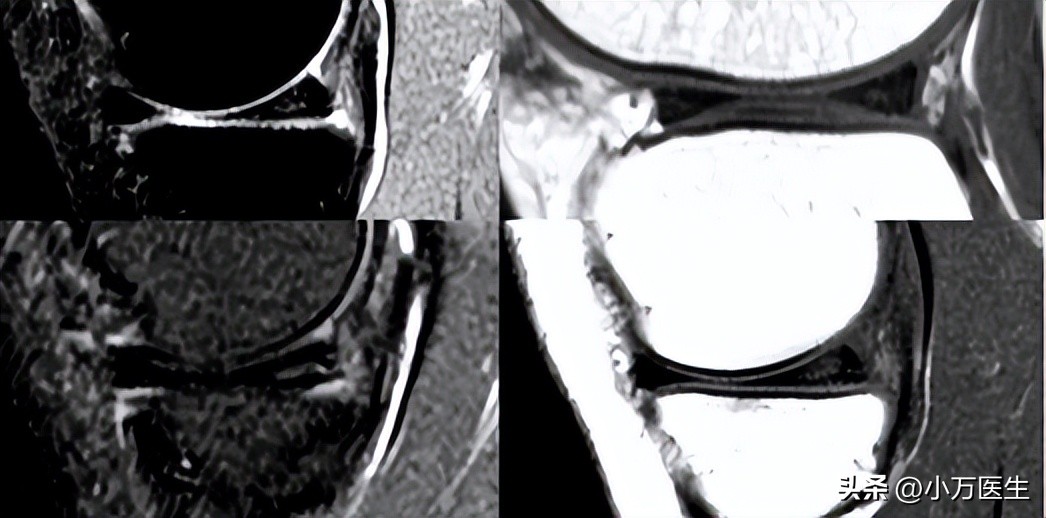

可以有效诊断半月板损伤,诊断准确率为90%。0-Ⅲ级法:Reicher MA和Lotysch于1986年首先提出。关节磁共振检查除了能发现半月板损伤外,同时还能发现关节内韧带、软骨以及关节外的病损,能有效减少漏诊机会。

0级:为正常的半月板,呈均匀的低信号,半月板形态规则。

(0级)

Ⅰ级:表现为不与半月板关节面相接触的灶性的椭圆形或球状的信号增高影。

(Ⅰ级)

Ⅱ级:表现为线性的半月板内信号增高,可延伸至半月板的关节囊缘,但未达到半月板的关节面缘-半月板内撕裂。

(Ⅱ级)

Ⅲ级:半月板内的高信号达到半月板的关节面,半月板的撕裂。

(Ⅲ级)